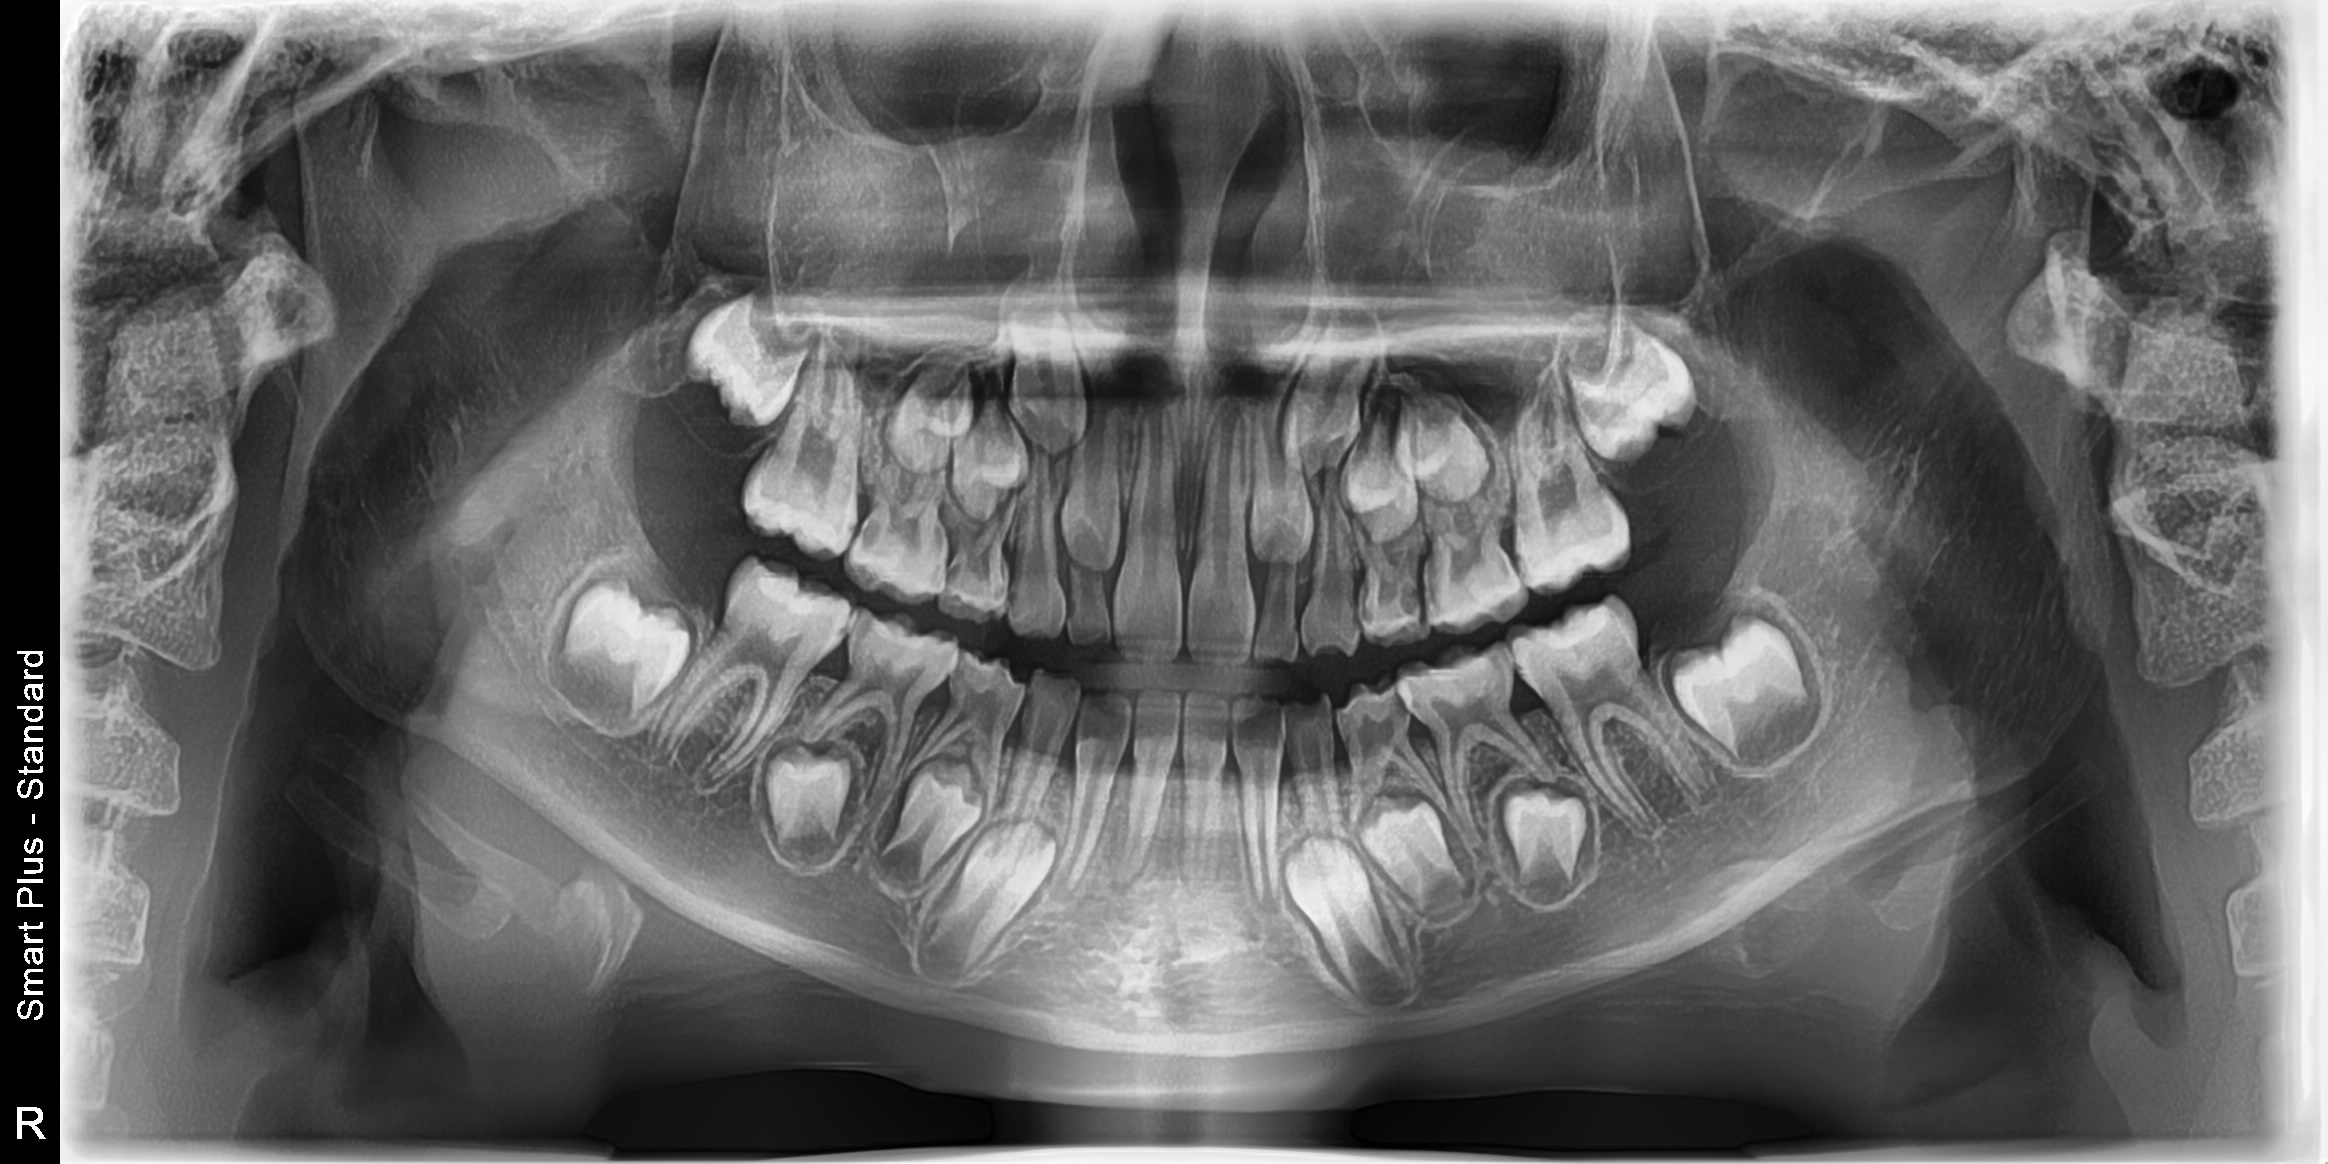

엄마인 제가 안일하게 치실을 안써서, 초등학교1학년(만7세8개월) 딸아이 어금니(영구치포함)에 모두 사이 충치가 생겼습니다. 선생님 책에도 치료가 필요하다고 하신 사이 충치입니다ㅠㅠㅠㅠㅠ

치과에 가보니 10개~13개정도 치료해야 한다고 합니다.(치료계획서 미호함된 오른쪽 아랫니도 포함 어금니전체)

영구치 빨리 치료해야 한다 하시고 영구치는 너무나 중요한데 썩었으니 약간씩 생긴 사이충치는 모두 떼우자고 하시고, 유치들은 신경치료 하고크라운으로 5개정도 하고, 나머지는 떼우자고 하시는데....

약간씩 생긴 영구치의 충치는 깨끗하게 치료하는데 맞는지,

육안으로 보이지도 않고 아프지도 않은 충치들 모두 제거 하는게 맞을까요?(육안으로 보이고, 과거 한참 아프다고 했고 현재는 안아프다고 하지만, 검은 구멍이 생기고 음식이 많이 끼는 불편한 곳은 왼쪽 윗니 뒤에서 두번째 사이입니다)

(영구치의 레진 치료가 필요한 상태인가요?

유치 중 신경치료가 필요한 이가 있을까요?)